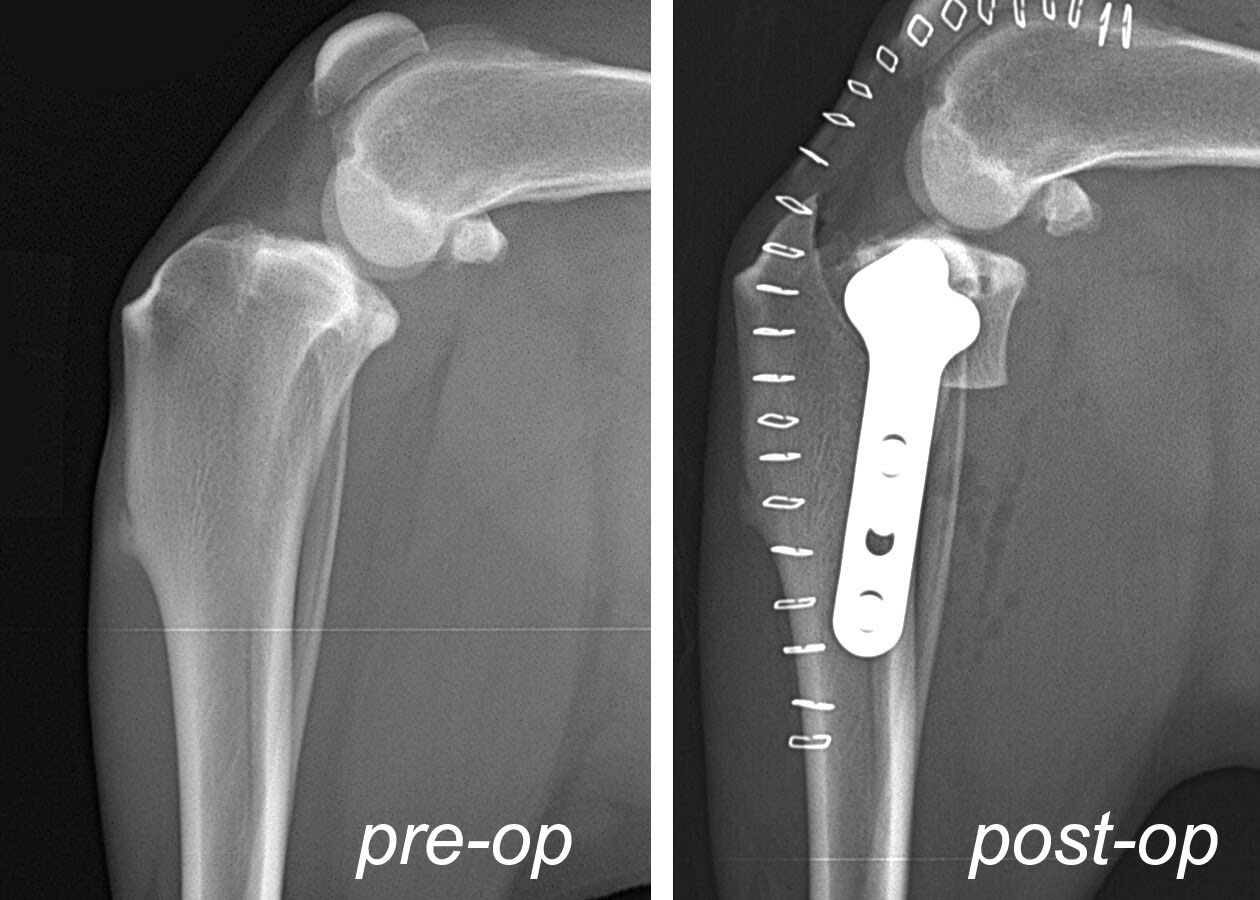

In the 1990’s, a procedure was developed by an Oregon based veterinarian called the tibial plateau leveling osteotomy, aka, TPLO. The procedure involves cutting a wedge of bone out of the head of the tibia, rotating it a predetermined number of degrees, and plating in place. This changes the physics of the knee by altering the angle of the surface of the head of the tibia (aka, tibial plateau), whereby the sheer force created by the injury is converted into a compressive force oriented toward the vertical axis of the femur. The resulting compressive force is not painful for the dog and successfully stabilizes the knee when the dog is weight bearing or in motion (stay tuned for more on the compressive force, as this is an important consideration). The subsequent reduction of the tibial slope accomplished by the TPLO also accounts for the aforementioned certain breeds that have steep tibial slope angles that predispose to CCL injury. The x-rays below show pre and post operative TPLO images.

Let’s return to TPLO for one moment before I close. Remember I wrote about converting the sheer force into a compressive force? No, it is not painful and, yes, it stabilizes the knee, but it is not without consequence. Over time that compressive force leads to earlier stage degenerative joint disease of knees surgically repaired via TPLO as compered to TTA and MMP. Also, look back at the TPLO x-ray and oberve the metal structures across the surface of the leg….those are skin staples necessary to close the skin and give you an idea of the size of the incision. That represents an 8-10 inch incision versus MMP that requires typically no more than a 3-4 inch incision.